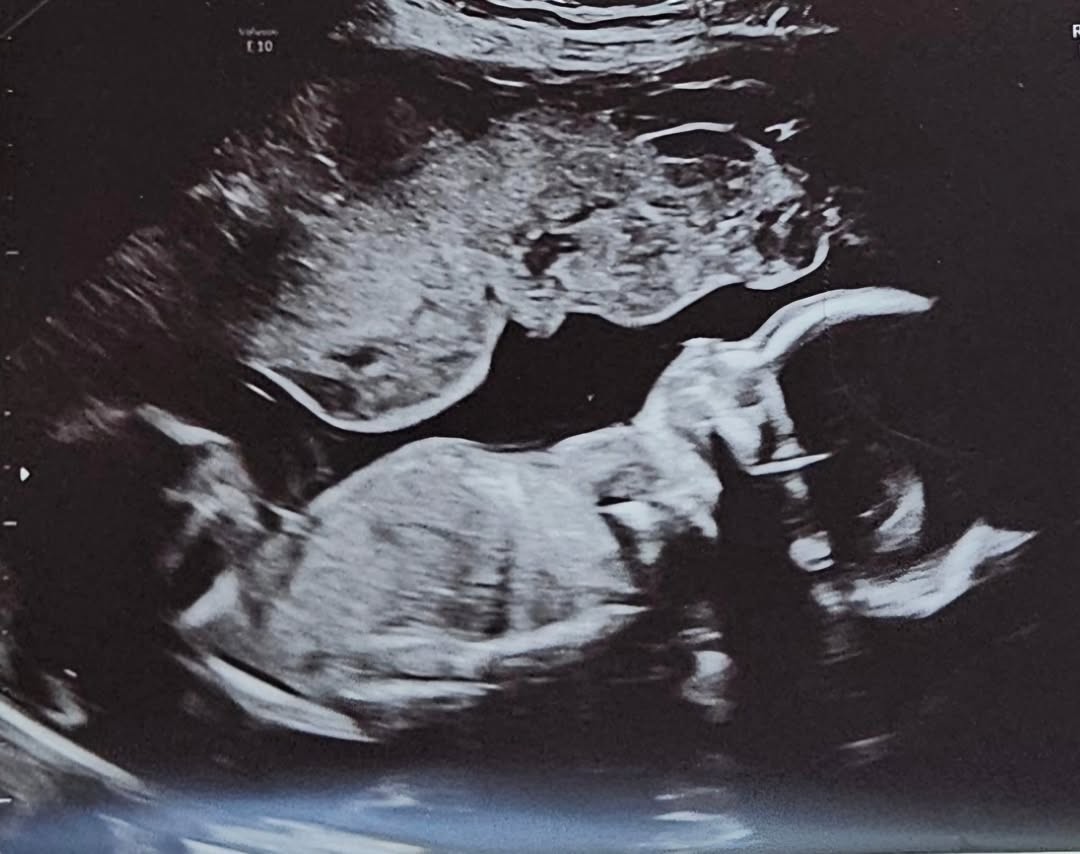

وُلدت الطفلة، التي أطلقت عليها اسم أفيانا روز، يوم الخميس 5 شباط/فبراير عند الساعة 6:09 مساءً، بوزن نحو 3.26 كيلوغرامات وطول يقارب 50.8 سنتيمتراً. وأعربت أوريكو في تصريحات لمجلة “PEOPLE” عن سعادتها بهذه اللحظة، ووصفتها بأنها أشبه بالحلم، لافتةً إلى أنها عاشت صراعات داخلية بين خوض التجربة منفردة أو انتظار شريك، إضافة إلى معاناتها سابقاً خمس حالات إجهاض، قبل أن يتحقق حلمها أخيراً.